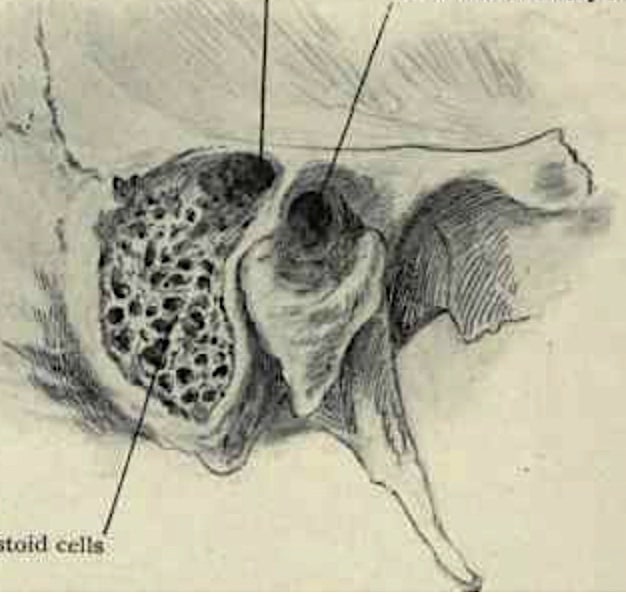

Анатомия сосцевидного отростка